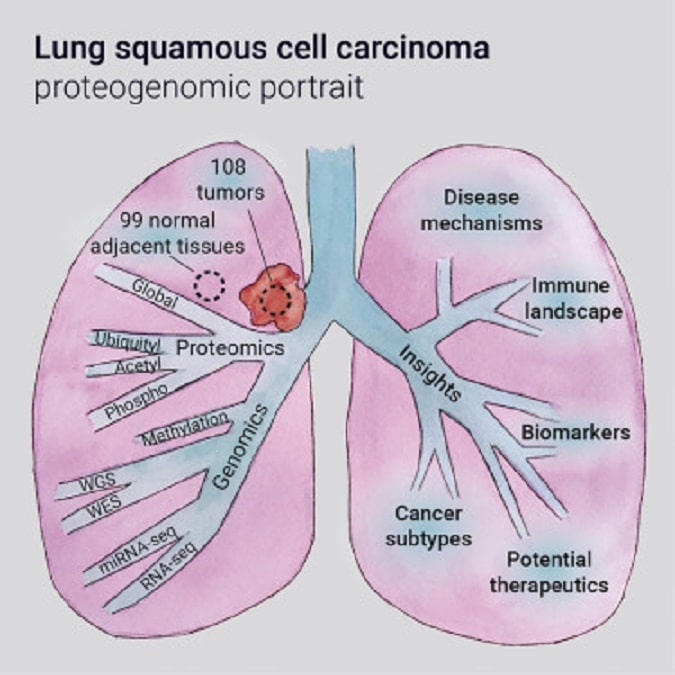

Καρκίνος του Πνεύμονα: Επιστήμονες του Ινστιτούτου Ιατρικών Ερευνών Garvan εντόπισαν μοριακά προφίλ της περιβάλλουσας μήτρας ενός κοινού τύπου καρκίνου του πνεύμονα, τα οποία μπορεί να υποδεικνύουν ποιοι ασθενείς είναι πιθανό να αναπτύξουν επιθετικούς όγκους. Το ακανθοκυτταρικό καρκίνωμα είναι ο δεύτερος πιο διαδεδομένος τύπος καρκίνου του πνεύμονα. Ωστόσο, οι θεραπευτικές επιλογές για αυτούς τους ασθενείς παραμένουν περιορισμένες και έχουν παραμείνει σε μεγάλο βαθμό αμετάβλητες επί δεκαετίες. Τα υψηλά ποσοστά υποτροπής και αντίστασης στη χημειοθεραπεία σημαίνουν ότι λιγότεροι από ένας στους πέντε ασθενείς θα επιβιώσουν περισσότερο από πέντε χρόνια μετά τη διάγνωσή τους.

Τα ευρήματα, που δημοσιεύονται στο Genomic Medicine, θα μπορούσαν ενδεχομένως να χρησιμοποιηθούν για την ανάπτυξη βιοδεικτών που θα καθορίζουν ποιοι ασθενείς θα μπορούσαν να επωφεληθούν από μια πιο επιθετική και πιο στοχευμένη θεραπεία. Η ομάδα, με επικεφαλής τον αναπληρωτή καθηγητή Thomas Cox, μελέτησε διεξοδικά τη μοριακή και πρωτεϊνική σύνθεση της μήτρας γύρω από τους όγκους του πλακώδους καρκινώματος του πνεύμονα, που ελήφθησαν από δείγματα ιστού ασθενών. Εντόπισαν δύο προφίλ μήτρας όγκου – ένα στο οποίο η πρόγνωση των ασθενών ήταν καλή και το άλλο στο οποίο οι ασθενείς τα πήγαιναν άσχημα. Αυτά τα προφίλ της μήτρας φαίνεται να δημιουργούνται νωρίς κατά την έναρξη του όγκου και να επιμένουν καθώς ο όγκος αναπτύσσεται, ελέγχοντας τον τρόπο με τον οποίο ο όγκος θα ανταποκριθεί στη χημειοθεραπεία. Η μήτρα του όγκου στους ασθενείς που τα πήγαν χειρότερα είχε περισσότερες πρωτεΐνες κολλαγόνου και περισσότερη ίνωση – ακαμψία της δομής του όγκου – γεγονός που υποδηλώνει ότι η μήτρα του όγκου αναδιαμορφώνεται για να προστατευτεί από τη θεραπεία.